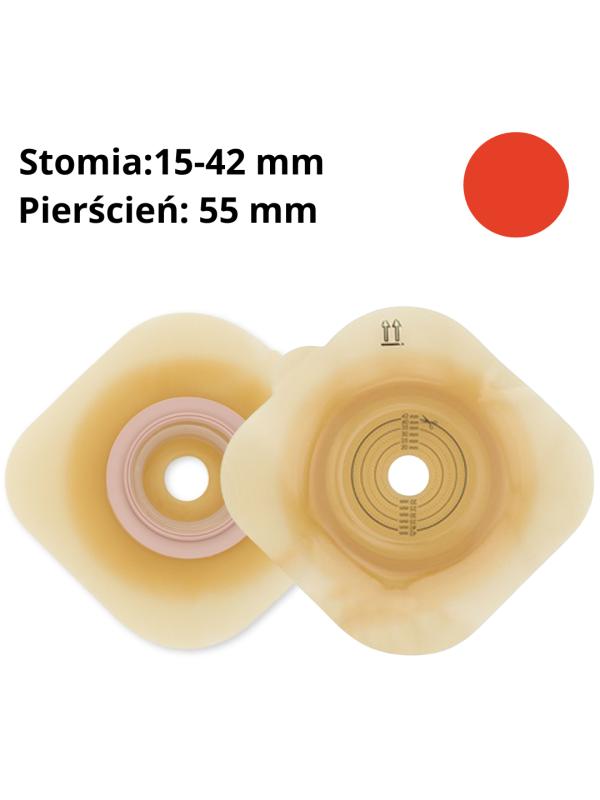

1155-15 Płytka stomijna Dansac Nova 2 Convex 55 mm wypukła, docięcie 15-42 mm

Płytka stomijna Nova™ 2 Convex 55 mm (1555-15)

Wypukła płytka do systemu dwuczęściowego – bezpieczne przyleganie, skuteczna ochrona skóry, pełna swoboda

Płytka stomijna Nova™ 2 Convex 55 mm to zaawansowane rozwiązanie dla osób z wklęsłą lub trudną do zaopatrzenia stomią. Dzięki wypukłemu profilowi (6 mm) i nowoczesnej barierze hydrokoloidowej GX, zapewnia pewne przyleganie, ochronę delikatnej skóry oraz bezpieczne i szczelne połączenie z workiem stomijnym. System sprzęgania „na klik” gwarantuje prawidłowe zapięcie i komfort noszenia każdego dnia.

Głębokość wypukłości 6 mm – pomaga wypchnąć stomię do wnętrza worka i zapewnia szczelność.

Możliwość docięcia – otwór startowy 15–42 mm, dzięki czemu płytka pasuje do wielu typów stomii.

Średnica pierścienia: 55 mm

Wymiary Płytki 1555-15 Dansac Nova 2 Convex:

WYPUKŁOŚĆ: 6 mm

OTWÓR STARTOWY: 15 mm

DO PRZYCIĘCIA: 15-42 mm

WYMIAR PŁYTKI (wys. x szer.): 115x115 mm